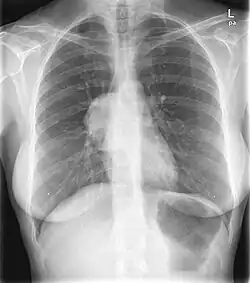

This PA chest radiograph demonstrates an abnormal contour in the right hilar region, with visualization of the pulmonary vessels through the mass (the hilar overlay sign) indicating its posterior mediastinal location. On resection this was found to be a benign solitary fibrous tumor of the pleura.

The hilum overlay sign is an imaging appearance on chest radiographs in which the outline of the hilum can be seen at the level of a mass or collection in the mid chest.[1] It implies that the mass is not in the middle mediastinum, and is either from anterior or posterior mediastinum(most of the masses arise from the anterior mediastinum).[2]